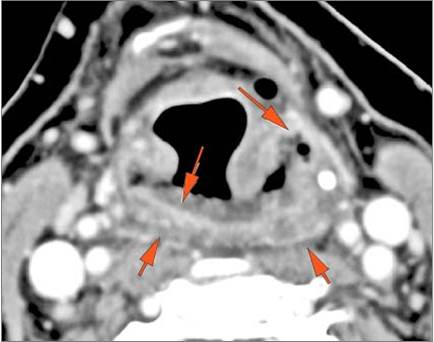

The upper lung zones and mediastinum visualized are abnormal. [Yes/No]